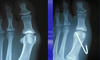

Name the procedure done:

Distal akin w/ 0.062 kwire